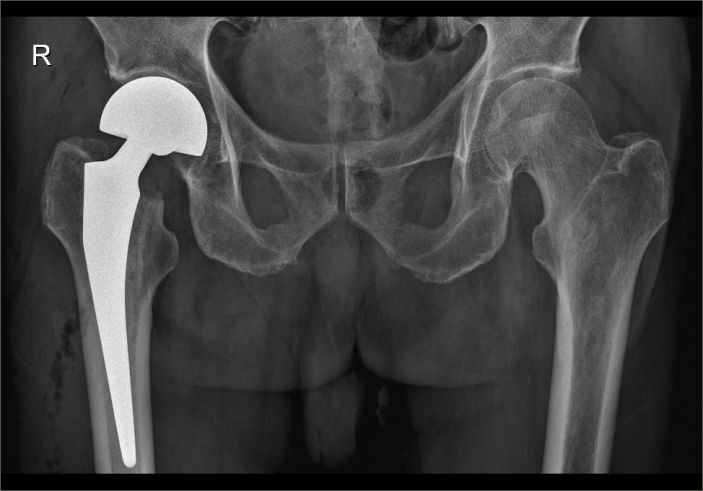

經過内科對症治療後,患者病情穩定,吳主任帶領團隊抓住時機,在麻醉科的配合下,果斷爲其施術。根據術前拟定方案按部就班實施手術,娴熟地切開組織、修整股骨近端、安裝骨柄假體和雙動股骨頭、複位髋關節,并細心檢查髋部活動度良好、雙下肢等長後,縫合切口順利完成手術。因術前準備充分,整個術程一氣呵成,既縮短手術時間,也減少術中出血,有效降低手術給患者帶來的傷害。